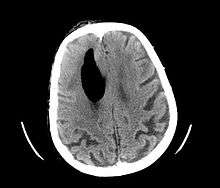

| Pneumocephalus and comminuted fracture of the frontal sinus | |

Pneumocephalus is the presence of air or gas within the cranial cavity. It is usually associated with disruption of the skull: after head and facial trauma, tumors of the skull base, after neurosurgery or otorhinolaryngology, and rarely, spontaneously. Pneumocephalus can occur in scuba diving, but is very rare in this context.

CT scans of patients with a tension pneumocephalus typically show air that compresses the frontal lobes of the brain, which results in a tented appearance of the brain in the skull known as the Mount Fuji sign.[1][2][3] The name is derived from the resemblance of the brain to Mount Fuji in Japan, a volcano known for its symmetrical cone. In typical cases, there is a symmetrical depression near the midline (such as the crater of a volcano), due to intact bridging veins.[3] Its occurrence seems to be limited to tension pneumocephalus (not occurring in pneumocephalus without tension).[4] The sign was first described by a team of Japanese neurosurgeons.[5]